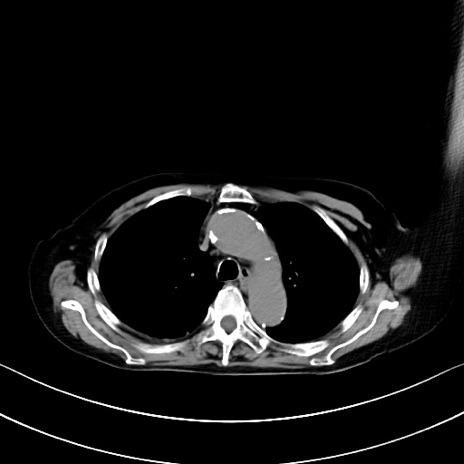

症例40(横断像)他院1日前

横断像

他院CT